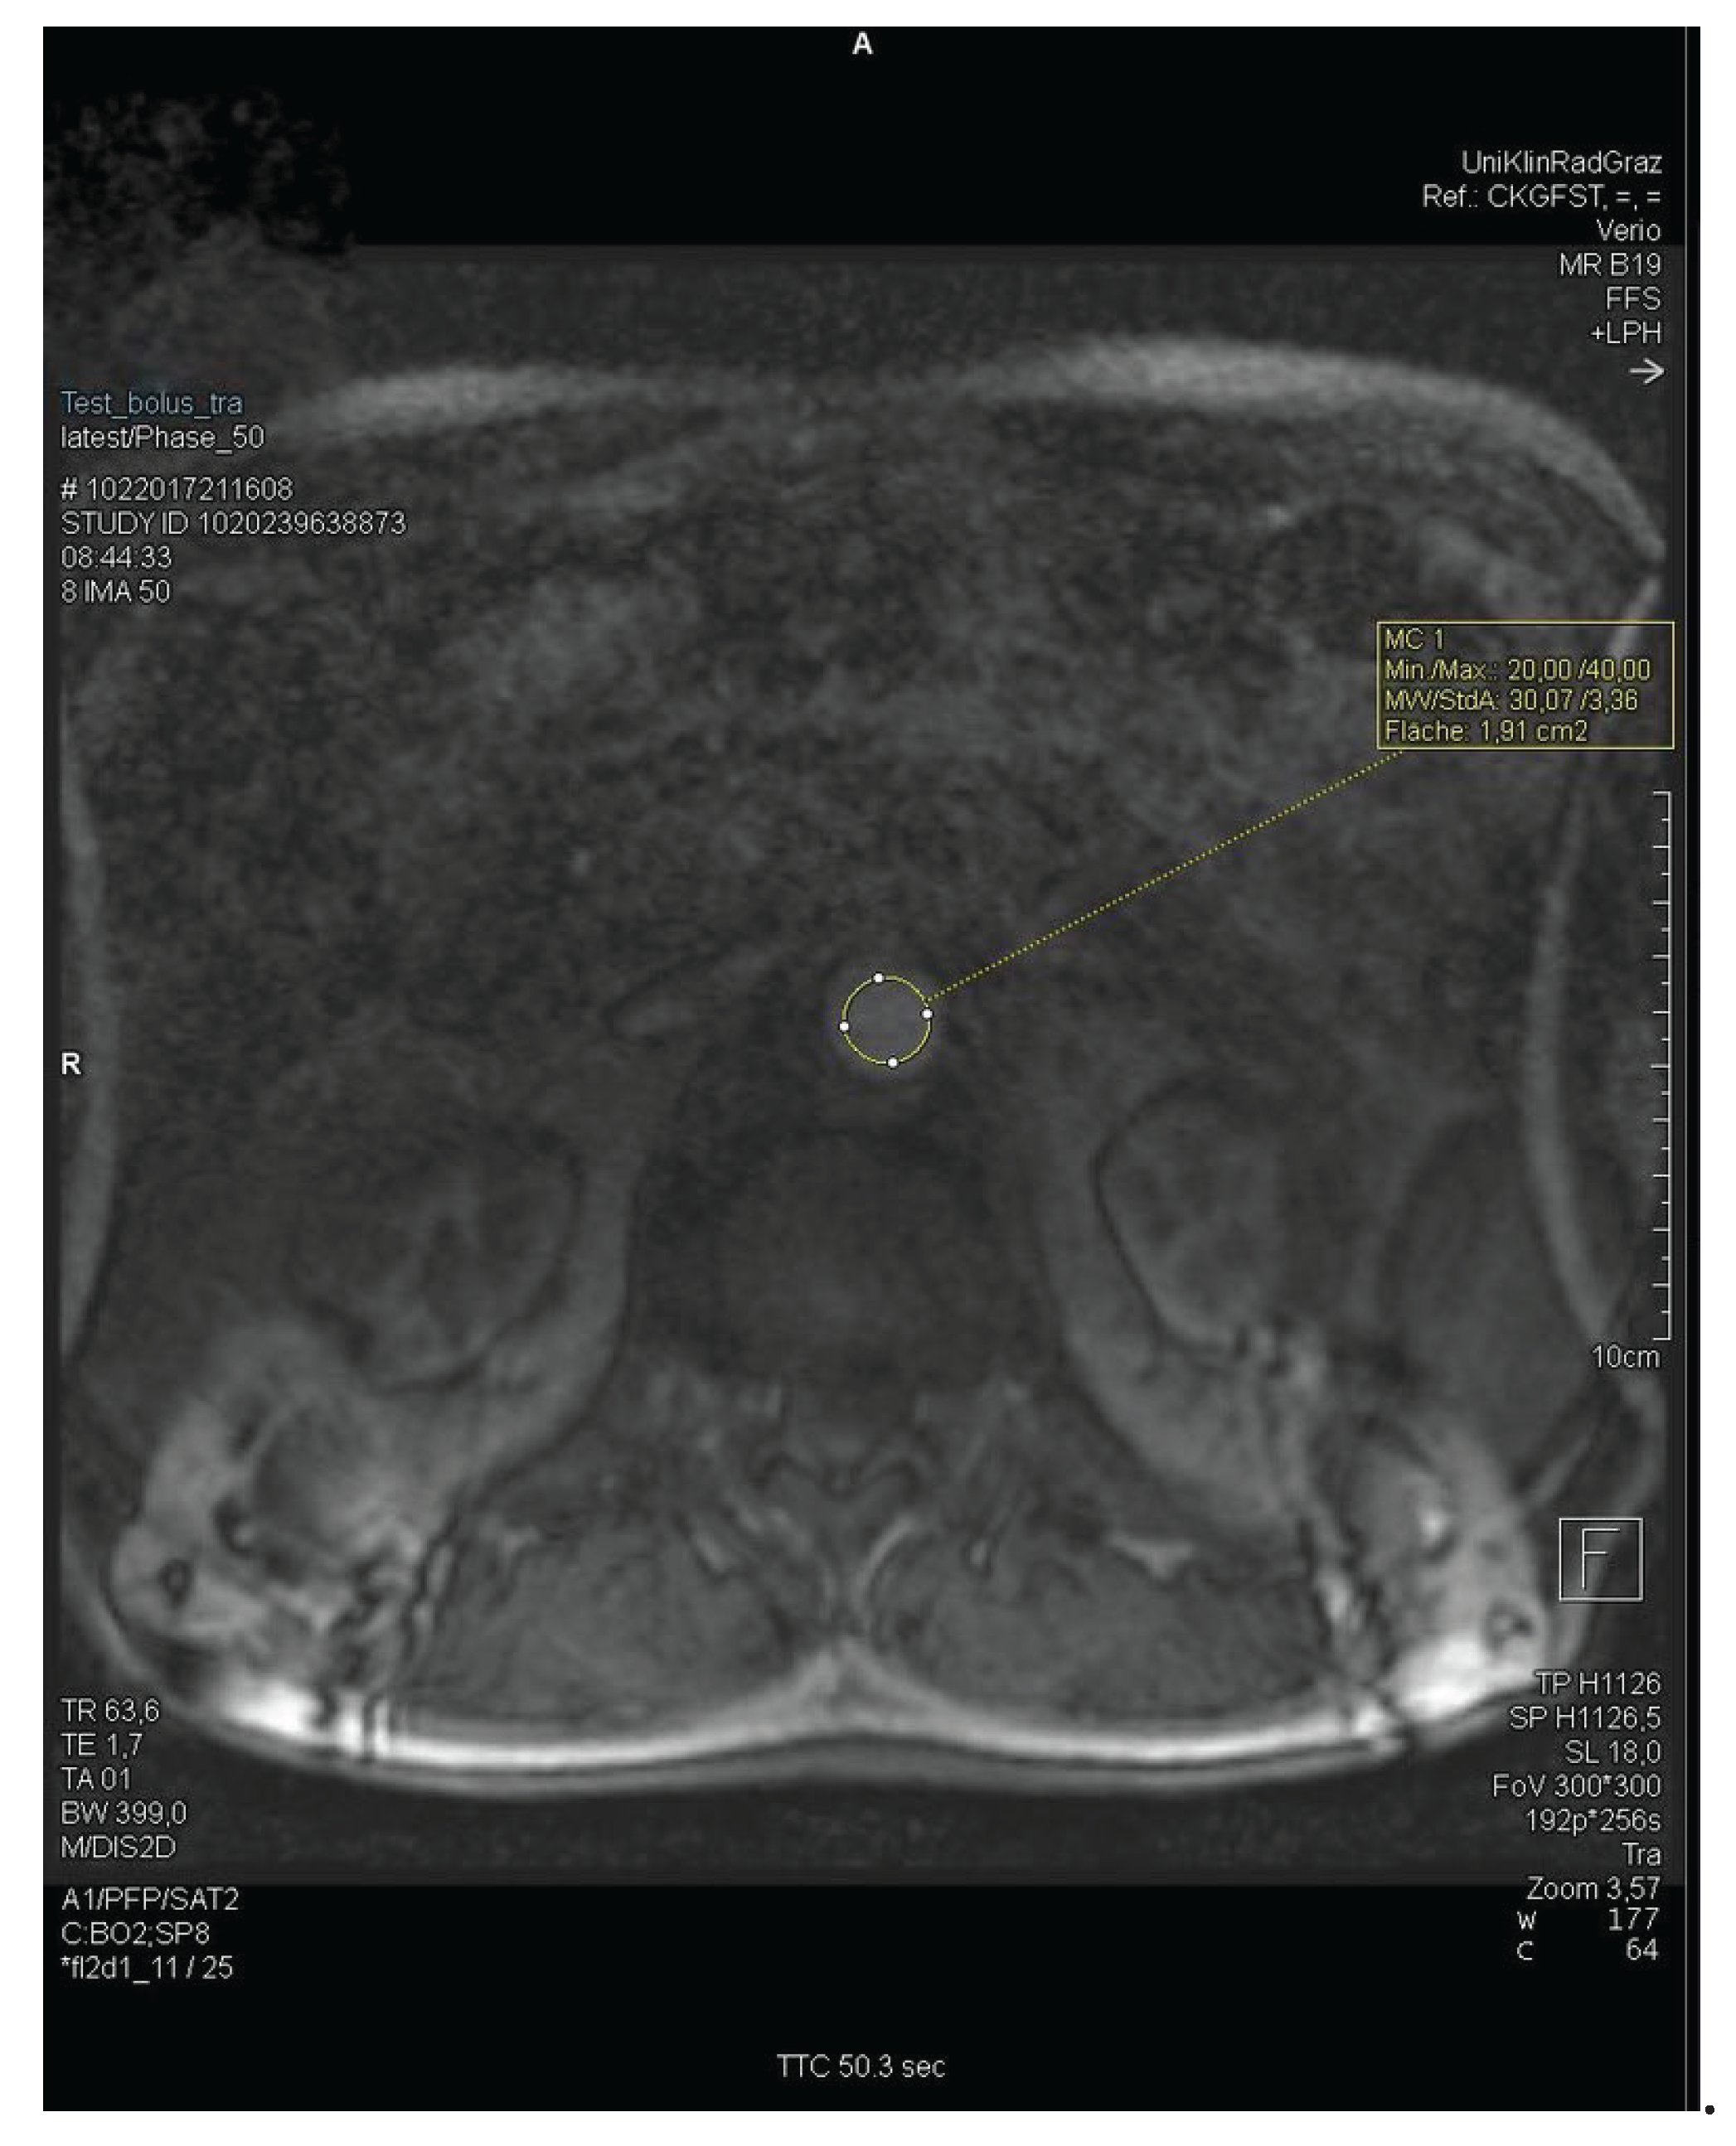

After establishing intravenous access and correctly positioning the patient in the MRI machine, the injection pump filled with contrast media is connected to the IV access. For CE-MRA, the "MEDRAD® MRXperion" injection pressure pump is used. Initial images are taken without contrast media for a preliminary overview of the body regions. The infusion pump is activated at a flow rate of 1.0 ml/s, 1.5 ml/s, or 2 ml/s, and simultaneously, a sequence of images from the abdominal aorta is captured every second. After 60 to 90 seconds, the image sequence capture is stopped. The ROI (region of interest) for determining the delay is located over the bifurcation of the abdominal aorta into the right and left common iliac arteries at the level of the kidneys or the branching of the renal arteries (Figure 1). The resulting graph shows signal intensity's rise, peak, and fall over time (Figure 2). The maximum signal intensity, defined as the TTP, is used as the delay time for the actual angiography. The TTP value is the peak measured by the graph.

In MEDOCS®, the delay was documented and recorded either in the documents of the radiology technicians or as part of the scanned protocols. If the test bolus was sent and saved as an image sequence with the MR images, the test bolus graph could also be analysed. The syngo.via® workstation (Siemens®) was used to analyse the TTP, full-width-half-maximum (FWHM) time, and the time the continuous signal increase began. For better readability, the start of the continuous signal rise is referred to below simply as "signal start." The height of the test bolus image sequence limited the plane of the ROI in the transverse section. For coronary sectioning, the ROI was set at the level of the kidneys and caudal to the renal arteries. An example of the ROI set in the abdominal aorta is shown here. Figure 1 shows the ROI at the level of the kidneys due to the transverse plane.

Figure 1. MRI of ROI set in the abdominal aorta at kidney level.